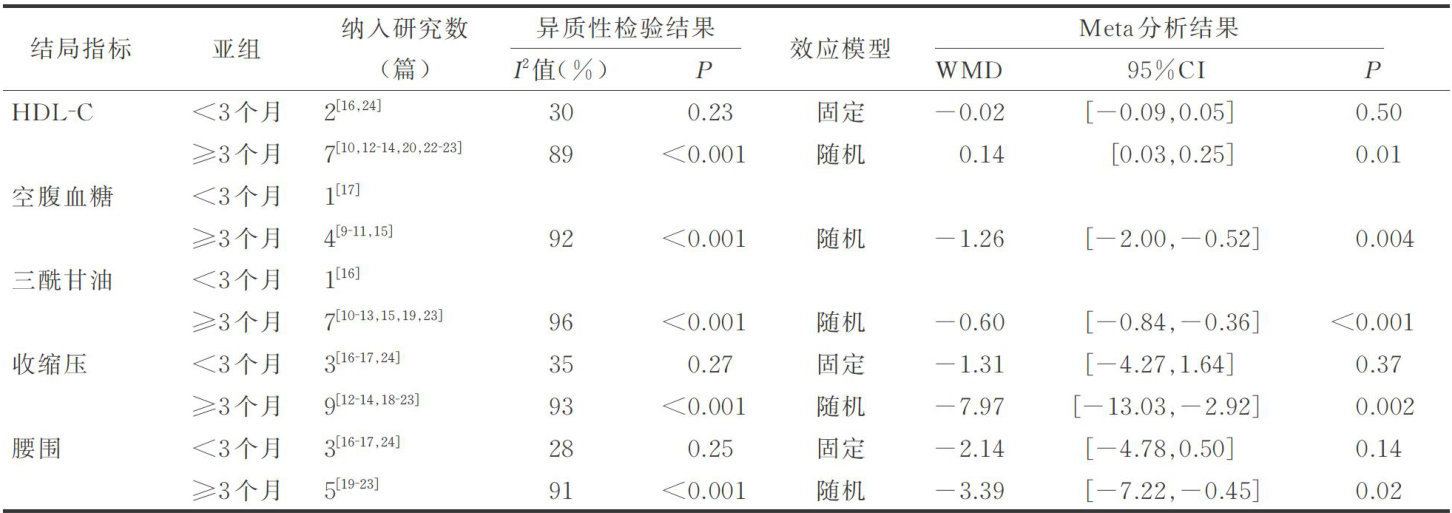

科研论著 | 生活方式干预对心血管代谢性共病病人影响的Meta分析

科研论著 | 生活方式干预对心血管代谢性共病病人影响的Meta分析